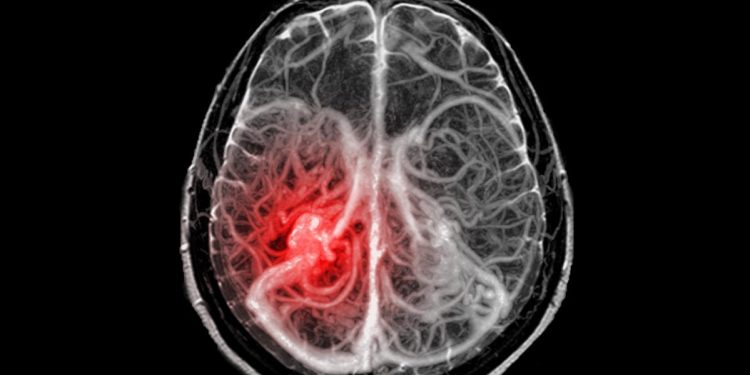

Redacción Ciencia, 17 nov (EFE).- Las terapias con células CAR-T han ofrecido buenos resultados en los cánceres de la sangre, pero no en los tumores sólidos. Ahora, un equipo de la Universidad de Stanford (Estados Unidos) ha probado con éxito esta inmunoterapia en un pequeño ensayo clínico para tratar tumores cerebrales infantiles incurables.

Estos resultados preliminares, con 11 niños y jóvenes afectados con un glioma difuso de línea media, se publican en la revista Nature. El tratamiento con células inmunitarias redujo el tamaño de los tumores cerebrales infantiles, restableció la función neurológica y, en el caso de uno de los participantes, borró todo rastro detectable de un cáncer cerebral considerado incurable.

Los gliomas difusos de la línea media, que pueden crecer en el cerebro o la médula espinal, se diagnostican en unos cientos de niños y adultos jóvenes en EE. UU. cada año, y tienen una supervivencia media de aproximadamente un año.

El DIPG, el subtipo de enfermedad que se produce en el tronco encefálico, tiene una tasa de supervivencia a cinco años inferior al 1 %. A medida que los tumores progresan, causan una profunda discapacidad.